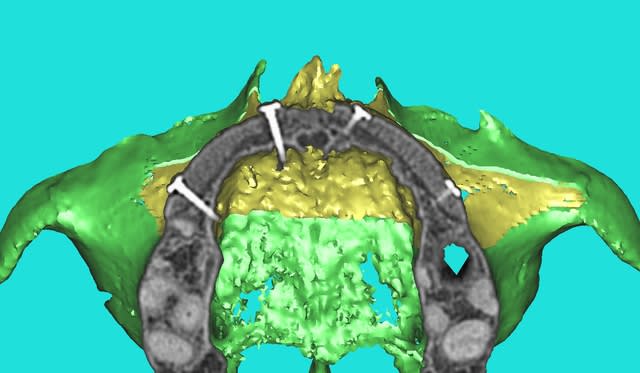

Dar axial lebnbu - Eugenol

Dar axiali qui1is - Eugenol

Dar11 cyo3el - Eugenol

Dar13 alznrp - Eugenol

Dar13i aujibg - Eugenol

Dar14 actm24 - Eugenol

Dar15 zvi82y - Eugenol

Dar23i g6nxds - Eugenol

Dar24 vzfroa - Eugenol

Dar25 lcptyk - Eugenol

Dar 3d xkb3uv - Eugenol

Dar  3di ngfcc4 - Eugenol

Dar  3dl fwmdk6 - Eugenol

Céramik

14/10/2011 à 01h09

image 8, il semble y avoir une zone entre le greffon et l'os ?

C'est intégré ?

Sinon, le cas semble bien, fait nous une vidéo !